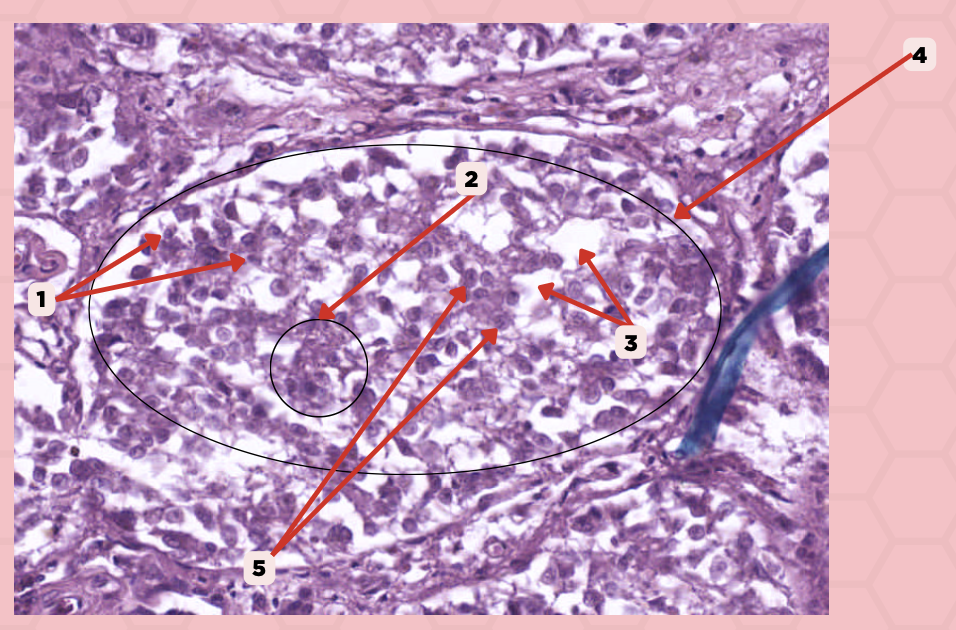

Pancreas

Identify the specimen.

Islets of Langerhans

Identify the structure labeled as 1.

Pancreatic Acini

Identify the structure labeled as 2.

Reticular Tissue

Identify the structure labeled as 3.

Pancreatic Duct

Identify the structure labeled as 1.

Reticular Tissue

Identify the structure labeled as 2.